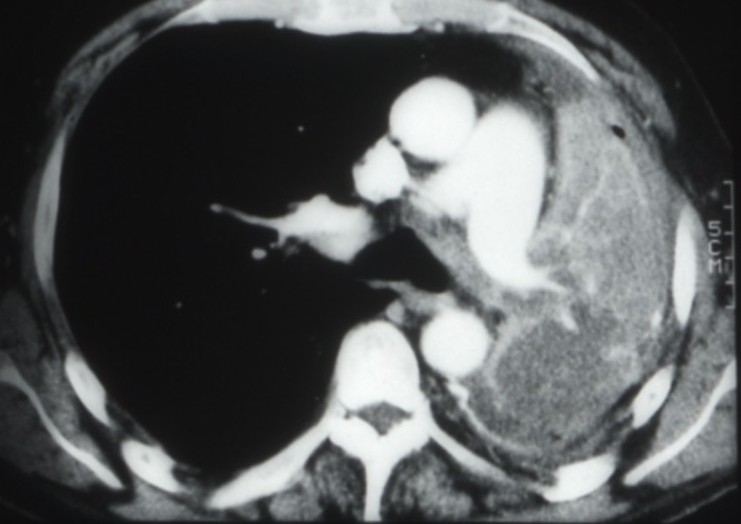

Cancers bronchiques